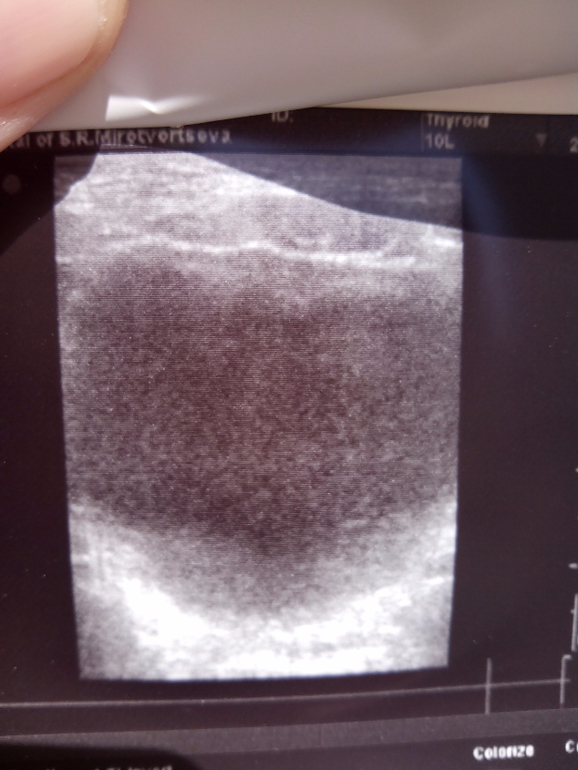

Вот снимки мочевого пузыря. Спасибо за внимание!